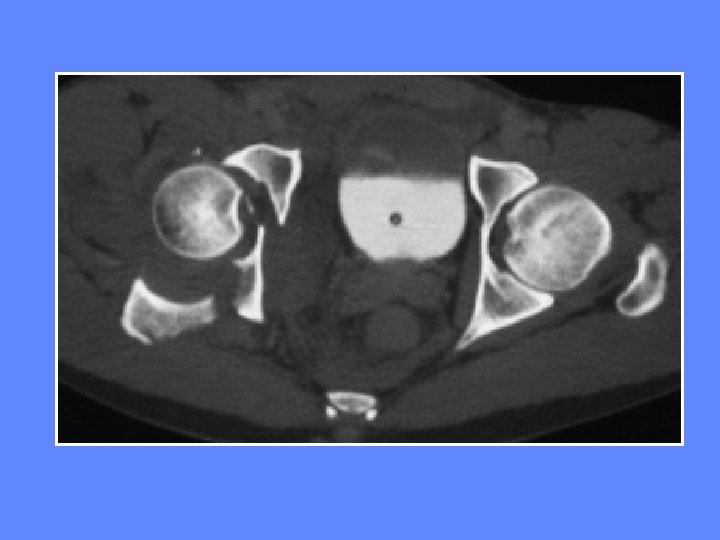

TDM luxation postérieure de la hanche